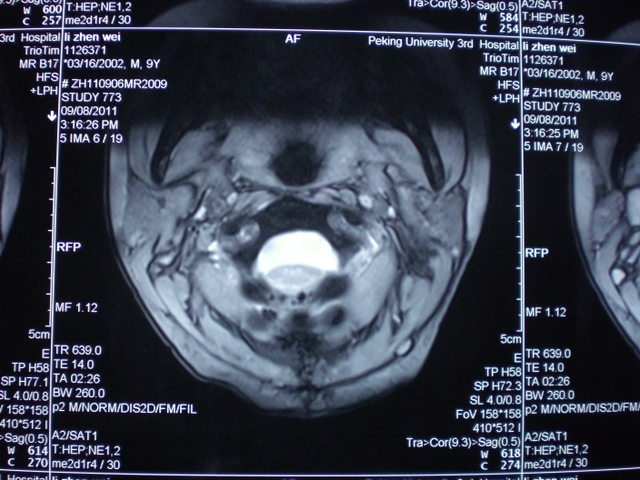

高颈段肠源性囊肿

高颈段肠源性囊肿高颈段肠源性囊肿